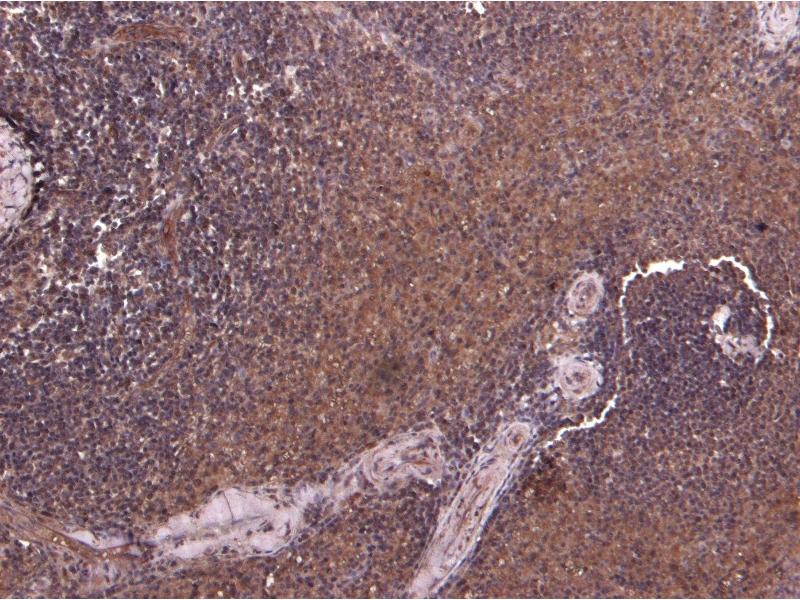

Immunohistochemistry: Paraffin embedded Human Spleen. Recommended concentration: 7 μg/mL.